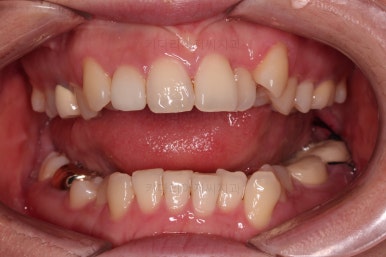

부산치과교정 키다리아저씨치과 초진 시 입안의 모습입니다.

확연히 좌우의 삐뚤어진 정도가 차이나죠.

덧니도 좌측(사진에서 보면 오른쪽) 위아래만 있는 상태고요.

좌측으로 삐뚤어져서 앞니도 좌측으로 쏠려 있는 상태였습니다.